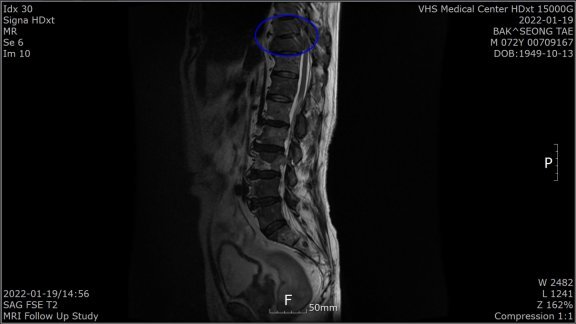

“1월 말 허리가 아파 병원에 갔더니 전립선암 말기라고 하더라고요. 전 베트남 참전용사로 국가유공자라 중앙보훈병원에서 진단 받았습니다. PSA(Prostate Specific Antigen·전립선 특이항원·전립선암의 선별검사 및 치료 판정을 위한 종양지표지자 검사)가 935 ng/mL라는 겁니다. PSA 4 ng/Ml 이하가 정상이라는데…. 너무 놀라서 그동안 아무 증상이 없었다고 했더니 전립선암은 증상이 없다 갑자기 나타난다고 하더군요. 전이가 돼 흉추 9, 10번이 시커멓게 썩었다고 하더군요. 참 나…. 방법이 죽을 방법 밖에 없다니. 하느님이 원망스러웠습니다.”

4월 29일 검사에서 PSA 수치가 0.059ng/mL로 떨어진 것이다. 그는 “MRI(자기공명촬영) 결과 새까맣던 흉추도 하얗게 정상으로 돌아왔다”고 했다. 말기암 판정 5개월여 뒤인 7월 29일 검사에선 PSA가 0.008 ng/mL로 떨어져 있었다.